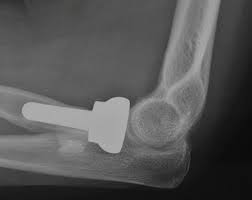

Σε πιο σοβαρές περιπτώσεις μπορεί να χρειαστεί οστεοσύνθεση με ειδικές μικρές πλάκες, αλλά σχεδόν πάντα μετά από τέτοιους τραυματισμούς παραμένει ένα ποσοστό δυσκαμψίας του αγκώνα. Στις πιο βαριές περιπτώσεις συντριβής της κεφαλής κερκίδας, κατά τις οποίες το κάταγμα είναι υπεράνω ανακατασκευής, ή αφαιρείται εντελώς η κεφαλή κερκίδας, ή αντικαθίσταται από μεταλλική κεφαλή.